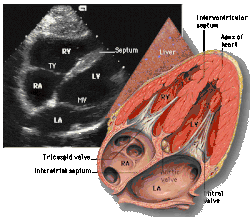

Apical four chamber (A4C)

This view is obtained at the apex of the heart and looking toward the base of the heart (where the valves are). In this view, the mitral valve, tricuspid valve, and all four chambers are visible. This view shows the right ventricle from base to apex and is a useful view to estimate RV systolic function. TAPSE (= tricuspid annular plane systolic excursion) is also measured in this view with M-mode through the lateral tricuspid annulus.

Structures:

- Inferior septum and anterior lateral segments of the left ventricle

- Right ventricle

- Left atrium

- Right atrium

- Mitral valve

- Tricuspid valve